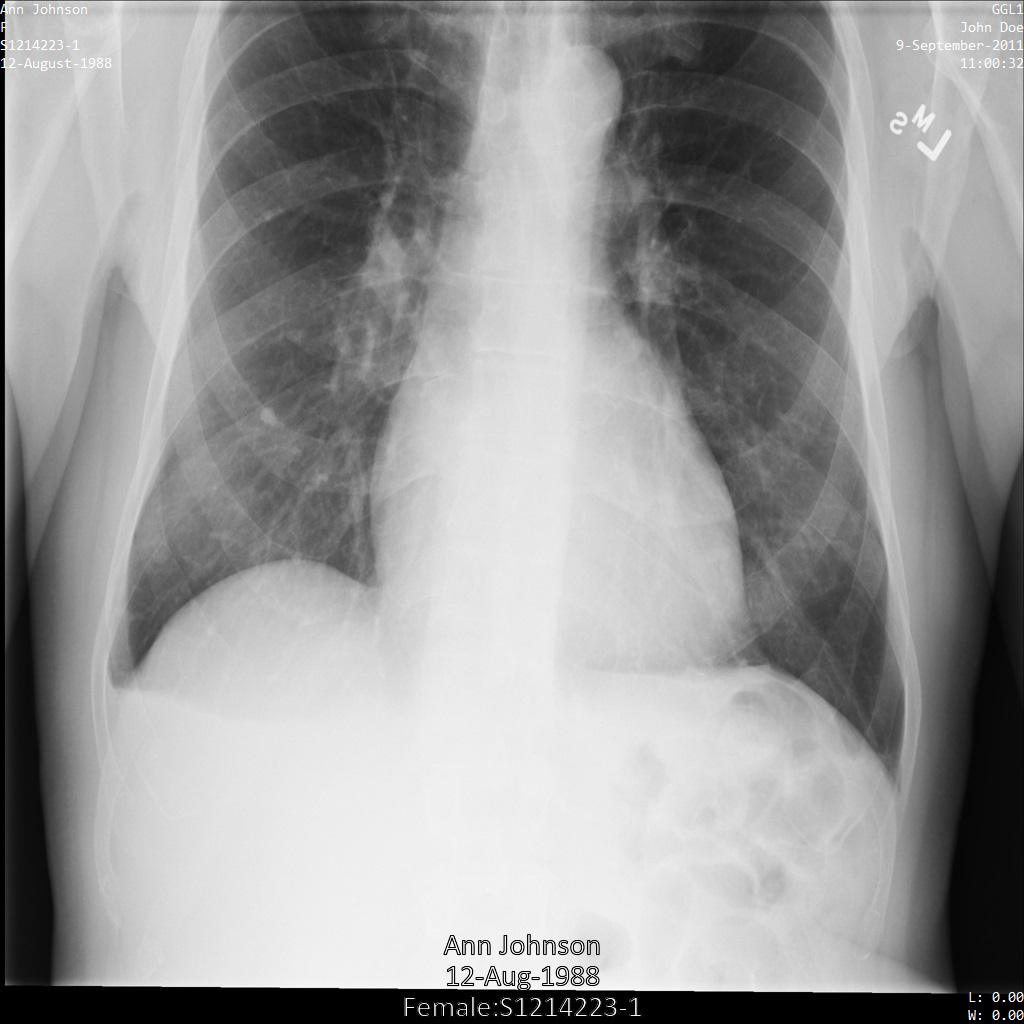

샘플 이미지

이 페이지의 일부 샘플에는 익명화된 이미지의 출력이 포함되어 있습니다. 각 샘플은 다음과 같은 원본 이미지를 입력으로 사용합니다. 각 익명화 작업의 출력 이미지를 이 원본 이미지와 비교하여 작업의 효과를 확인할 수 있습니다.